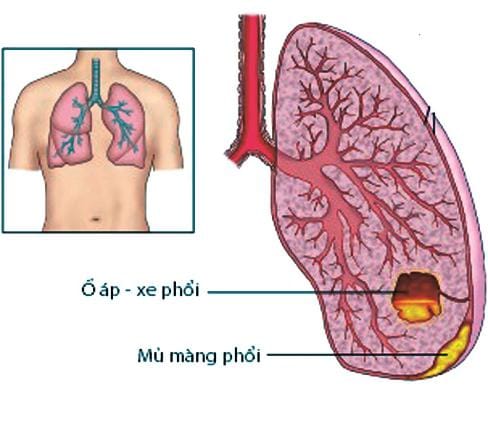

4. Biến chứng tràn mủ màng phổi

Nếu trẻ bị tràn mủ màng phổi cần phải được chẩn đoán và điều trị sớm, điều này giúp tránh được biến chứng lâu dài như: Khả năng giãn nở của phổi và chức năng hô hấp của trẻ.

Các biến chứng có thể gặp là rò khí quản - màng phổi, áp xe phổi, viêm mủ màng ngoài tim… Ngoài ra, trẻ có thể gặp các biến chứng viêm xương sườn, vẹo cột sống tạm thời, nhiễm khuẩn huyết…

5. Nguyên tắc điều trị tràn mủ màng phổi

Tràn dịch màng phổi là bệnh lý thường gặp ở trẻ và hoàn toàn có thể điều trị khỏi. Tùy từng trường hợp, mức độ bệnh mà các bác sĩ sẽ chỉ định cụ thể với từng bệnh nhi. Tuy nhiên, với nguyên tắc là hỗ trợ hô hấp, tuần hoàn, kháng sinh sau chọc dò màng phổi, đặt dẫn lưu màng phổi sớm, can thiệp ngoại khoa và cuối cùng là vật lý trị liệu… Vì vậy, việc thực hiện nghiêm túc các chỉ định điều trị của các bác sĩ là vô cùng quan trọng.

Nếu trẻ đến viện sớm, việc điều trị sẽ hiệu quả và đơn giản. Còn nếu trẻ nhập viện muộn, thì việc điều trị sẽ khó khăn vì dịch mủ đã tạo thành các khoang vách, nên chọc hút hay dẫn lưu sẽ không kết quả… trẻ cần được phẫu thuật để làm sạch mủ trong khoang màng phổi. Tuy nhiên, phẫu thuật mở ngực ở trẻ nhỏ tiềm ẩn nhiều nguy cơ và về lâu dài vẫn ảnh hưởng đến chức năng hô hấp của trẻ. Ngoài ra, trẻ còn có nguy cơ bị dày dính màng phổi sau này.